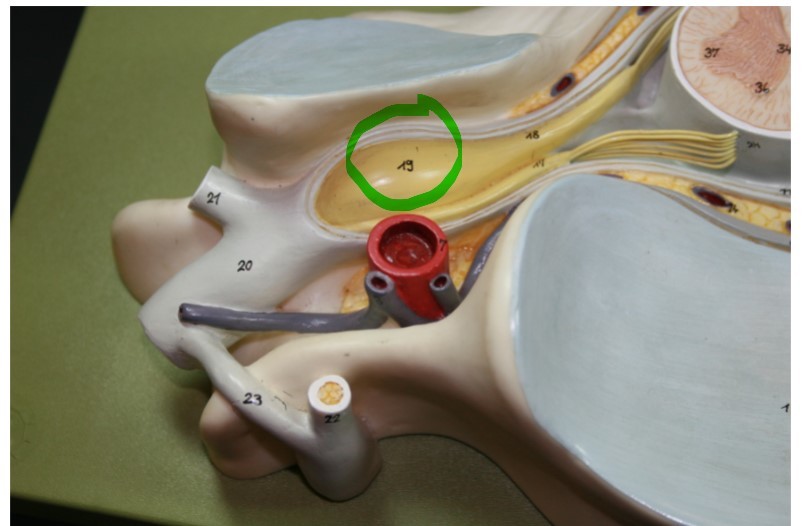

Spinal cord - dorsal root ganglion

where the cell bodies of sensory neurons are located; attached to posterior root